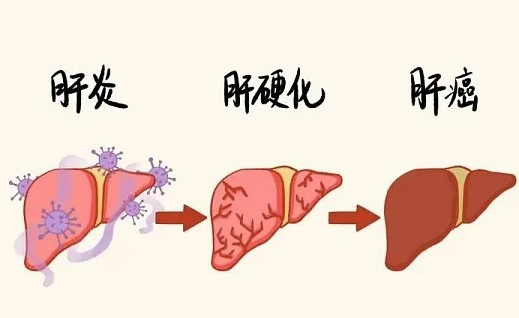

肝癌:“隐身杀手”,复发率超七成

肝癌早期几乎没症状,很多人发现时已经是中晚期。就算做了根治手术,肝内也可能残留微小病灶,加上多数患者有乙肝、丙肝或肝硬化,肝脏的 “土壤” 本身就容易长肿瘤。

数据显示,肝癌术后 5 年复发率高达 60% 到 80%。有乙肝、丙肝的患者,术后一定要坚持抗病毒治疗,每 3 到 6 个月查一次增强 CT 或 MRI,还要定期测甲胎蛋白,别等有症状了才去医院。